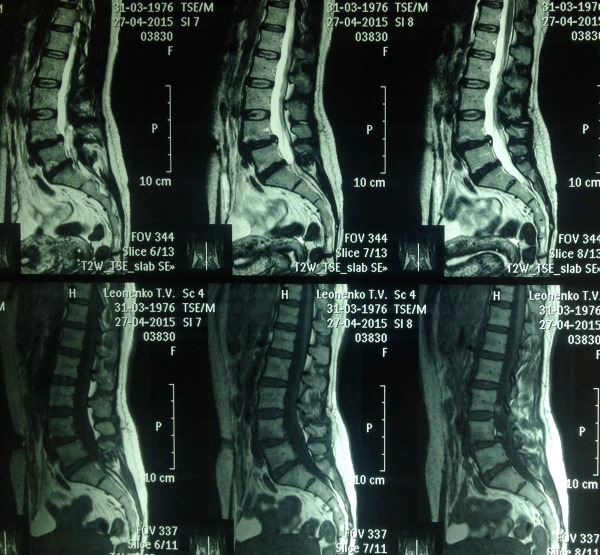

Наиболее наглядно нестабильность позвоночника можно увидеть на МРТ-снимках, выполненных в положении стоя.